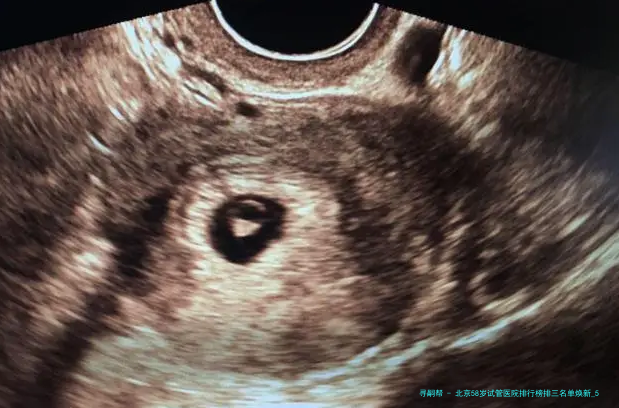

“医生,我58岁AMH值几乎为零,仍旧有可能用自己的卵子做试管吗?”在北京某生殖中心咨询室,一位鬓脚花白的女士紧握化验单的手悄悄发抖——这便是很多超高龄家庭求子路的真实缩影💔。58岁生育堪称“逆天改命”🧬:卵巢功效彻底衰竭、胚胎染色体不同寻常率超80、妊娠并发症风险迅猛上涨……选错医院不仅人财两空,更可能错失后的生育机会!2025年北京具备试管资质的医院达18家,但真实擅长超高龄方案的仅寥寥数家。本文结合新临床数据,揭晓严选前三医院排行、反转策略与性价比方案,让每一分盼望都用在刀刃上!

58岁试管成功的重要在于医院是否拥有个别化促排方案、胚胎基因学筛查(PGT)技术、多科目并发症处理能力。根据2025年北京市辅助生殖质量报告,下面列举三家医院在超高龄领域表现突出(按技术储备、临床数据、患者口碑综合排序):

北京大学第三医院生殖中心中国试管婴儿技术发源头所在地,针对五十八岁病人推出“微刺激+胚胎累积”方案,2025年临床妊娠率达15-18。其胚胎实验室配置时间间隔成像系统(Time-lapse),可动向筛选优质胚胎,专业人士乔杰院士团队在高龄遗传病筛选领域经验丰富。

北京协和医院生殖医学中心疑难病例处置标杆,选用“两重促排方案”应对卵巢低反映,联合内分泌科取代策略。2025年数据显现,超高龄病人活产率稳固在12-15,其胚胎冷冻苏醒率达98。

解放军总院第6个医学中心军属绿色通道与应急保障,具有全军生殖医学关键要点实验室。针对五十八岁患者采用“天然周期采卵+胚胎玻璃化冷冻”技术,积聚妊娠率提高20,费用透明(单周期六万至九万元含补贴)。